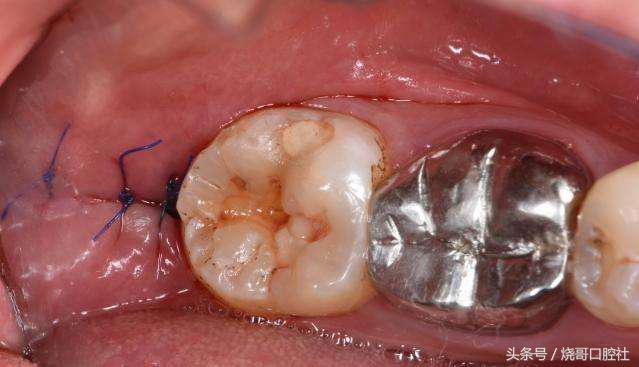

2、不管拔牙部位在前牙还是后牙,拔牙窝恢复后再镶牙或种牙已经失去意义,要知道镶牙和种牙最怕的就是牙周炎,就像土壤都没有了,怎么固定住牙根?

3、如果创口是智齿位置,那有可能会引起干槽症,明显拔牙后3~4天创口痛感会更加强烈,而且缝合线附近溃疡有异常的暗灰色,有时还能感觉到臭味。

那究竟怎么治疗好干槽症?

既然是致病菌感染引起,就得再用重新清洗的方式,用生理盐水冲洗创口,特别是牙槽骨壁,再添加过氧化氢溶液反复来回清理,最后放入一个碘仿纱条,这样才会长出新的肉芽组织,很快3个月左右牙槽窝就能慢慢愈合长平。